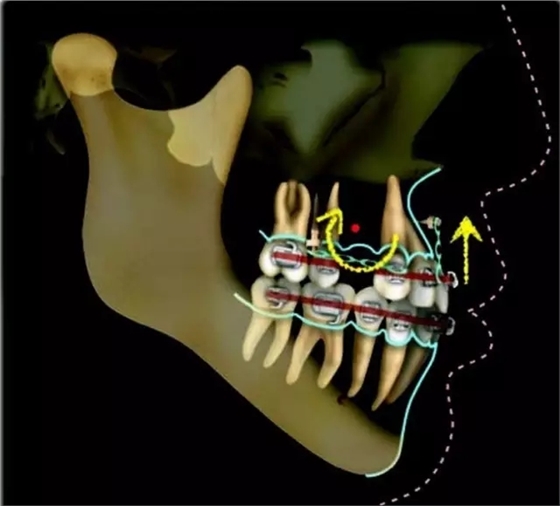

上下牙列擁擠,磨牙尖牙Ⅱ 類關(guān)系,3 度的深覆牙合,上頜中切牙伸長內(nèi)傾拔除上頜雙側(cè)的第一前磨牙,先粘上頜高轉(zhuǎn)矩的自鎖托槽排齊牙列,唇向開展上頜切牙,有一定的覆蓋,粘下頜標準轉(zhuǎn)矩托槽,上頜 1, 2 之間植入種植支抗壓入,同時后牙 5, 6 之間植入種植支抗內(nèi)收前牙,打開咬合關(guān)閉間隙。治療關(guān)鍵:前牙轉(zhuǎn)矩的控制第 1 個月 上頜粘上 Damon Q 高轉(zhuǎn)矩托槽,上 .014 熱激活 NiTi 絲。第 3 個月 上換 .014 x .025 熱激活 NiTi 絲。第 5 個月 上頜基本排齊,覆蓋增大,上換 .017 x .025 NiTi絲,下頜粘托槽,下 .014 熱激活 NiTi 絲。第 7 個月 上 .017 x .025 NiTi 絲加搖椅,下?lián)Q .014 x .025 熱激活 NiTi 絲第 9 個月 上頜換 .019 x .025 NiTi 絲加搖椅,下頜換 .017 x .025 NiTi 絲第 11 個月 下頜換 .019 x .025 加搖椅,上頜 1, 2 之間, 5, 6 之間植入種植釘,下頜出現(xiàn)散隙。第 13 個月 上頜換 .019 x .025ss 加搖椅,前牙種植釘用 Power Chain 壓低前牙(每側(cè) 100g),后牙種植釘關(guān)閉間隙(每側(cè) 150g),下?lián)Q .019 x .025ss,Power Chain 關(guān)閉間隙。第 19 個月 上頜前牙基本壓低到位去除前牙種植釘,繼續(xù)用關(guān)閉間隙,下頜散隙關(guān)閉。

第 22 個月 上頜覆蓋變小,去除 5, 6 之間種植釘,后牙前移關(guān)閉間隙。第 30 個月 患者未配合中線牽引,下中線仍有 1mm 右偏,患者對矯治效果滿意要求拆除,拆除固定矯治器,取模制作壓模保持器。 1.骨性 Ⅱ 類的患者內(nèi)收前牙時需對上頜前牙的轉(zhuǎn)矩進行較好的控制才能獲得良好的面型和唇部形態(tài)。 2.露齦笑的患者治療前要分析其病因是唇、牙齦、牙齒、牙槽骨、上頜骨或多種因素結(jié)合,再制定矯治方案。 3.Ⅱ 類第二分類伴露齦笑的患者的上頜前牙移動軌跡是唇向開展-壓低-整體內(nèi)收。 4.Ⅱ 類第二分類牙齒舌傾比較厲害的情況,上頜中切牙慎用樹脂咬合墊。 5.壓低前牙或控根移動時容易發(fā)生牙根的吸收,需輕力緩慢的移動。